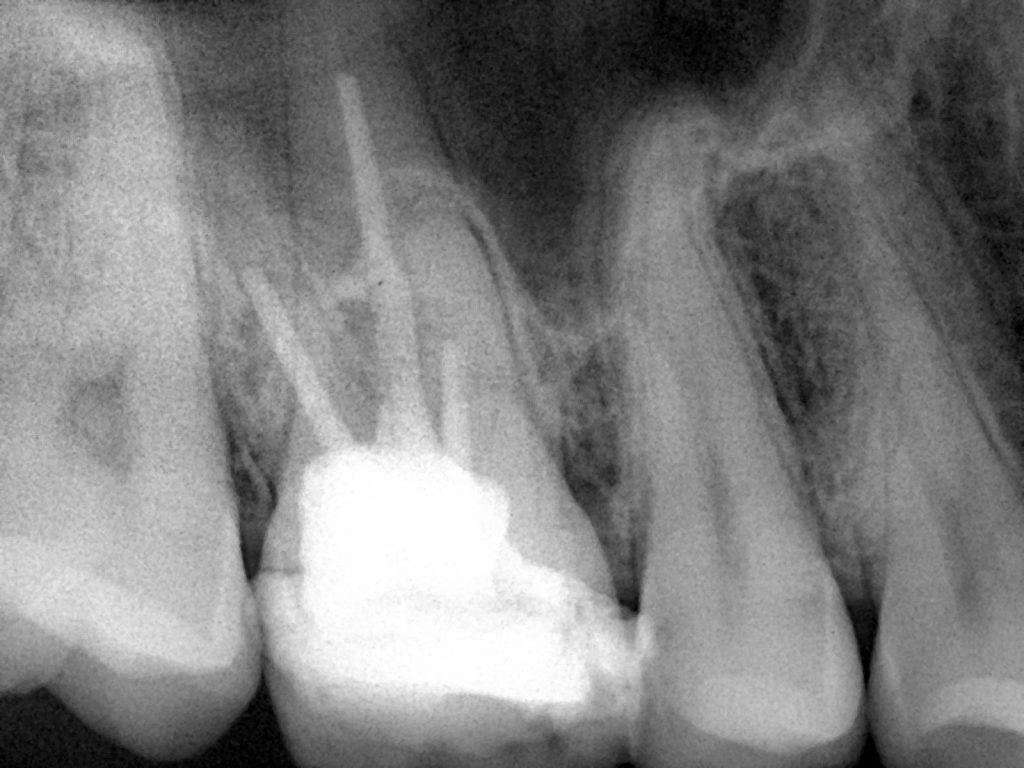

بعد التشخيص بالأشعة السينية والأشعة السينية

لقد أظهرت نتائج سيئة وقنوات متكلسة

Preoperative x-ray

Post operative x-ray after r.c.t done